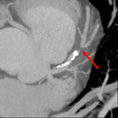

Cardiac CTA

A coronary blockage is seen at the arrow.

|

The same blockage can been seen in different angles.